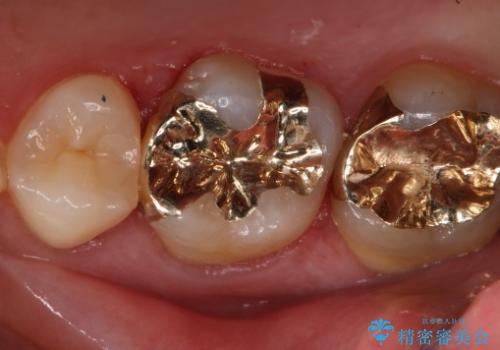

- 右上6番の銀歯のやりかえを希望し来院された患者様です。

切削量や形状からインレーでの治療を計画しました。

ご本人が金歯を希望されたため、ゴールドインレーでの治療を選択しました。